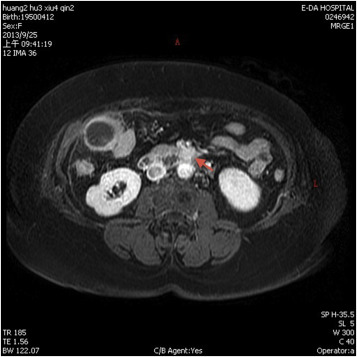

A 64-year-old woman with past medical history significant for hypertension had visited the emergency department many times over the course of several years due to intermittent hypertensive emergencies. On this presentation, she was admitted with features of symptomatic cholelithiasis. Abdominal ultrasound confirmed the presence gallstones and incidentally showed a 1.5-cm hypoechoic mass in the uncinate process of the pancreas (Figure 1 ). A physical examination was unremarkable except for mild right upper quadrant tenderness and elevated blood pressure (211/112 mmHg). Serum carcinoembryonic antigen and carbohydrate antigen 19-9 levels were both within normal limits. Contrast-enhanced computer tomography showed a 1.6-cm enhancing mass in the uncinate process of the pancreas (Figure 2 ). On magnetic resonance imaging, the lesion was identified as a 1.6-cm low-intensity mass on T1-weighted imaging and a slightly high-intensity mass on T2-weighted imaging. Magnetic resonance imaging with contrast enhancement revealed that the lesion was enhanced (Figure 3 ). On the basis of these findings, preoperative diagnosis was a pancreatic hypervascular tumor, suspected to be a neuroendocrine tumor. A pylorus-sparing Whipple procedure was recommended to achieve complete excision of the tumor and to treat the symptomatic cholelithiasis. Grossly, an oval and well encapsulated tumor measuring 1.5 cm in greatest dimension was noted within the lower part of uncinate process. Microscopically, this well-encapsulated tumor was composed of proliferation of polygonal cells arranged in trabecular, nest, and alveolar patterns separated by a stroma rich in vascular network. The tumor cells had an amphophilic-to-basophilic cytoplasm. Tumor nuclei were round to oval with moderate nuclear pleomorphism and prominent nucleoli (Figure 4 ). Mitotic figures were not identified. Capsular and vascular invasion was not present. By immunohistochemical staining, the tumor cells were reactive to CD 56, synaptophysin, and chromogranin A. The sustentacular cells surrounding the tumor clusters were also highlighted by immunostaining for S100. The lymph nodes dissected were free of malignancy. Both histomorphology and immunoprofiles of the tumor were typical of paraganglioma. Hypertensive urgency developed after the operation which was controlled with continuous intravenous nicardipine. Collected 24-h urine catecholamine data showed that norepinephrine levels were 175 μg/day (normal value: <97 μg/day) and vanillylmandelic acid levels were 8.06 mg/day (normal value: 1–7.5 mg/day). After 7-day nicardipine treatment, we gradually shifted to oral antihypertensive agents. Finally, the patient was successfully discharged with oral doxazosin (4 mg) one tablet per day. The patient had no clinical signs, symptoms, or family history suggestive of multiple endocrine neoplasia or Von Hippel–Lindau disease.

Figure 3. Magnetic resonance imaging with contrast enhanced (T2 weighted) revealed an enhancing lesion (arrow) in the uncus of the pancreas. |